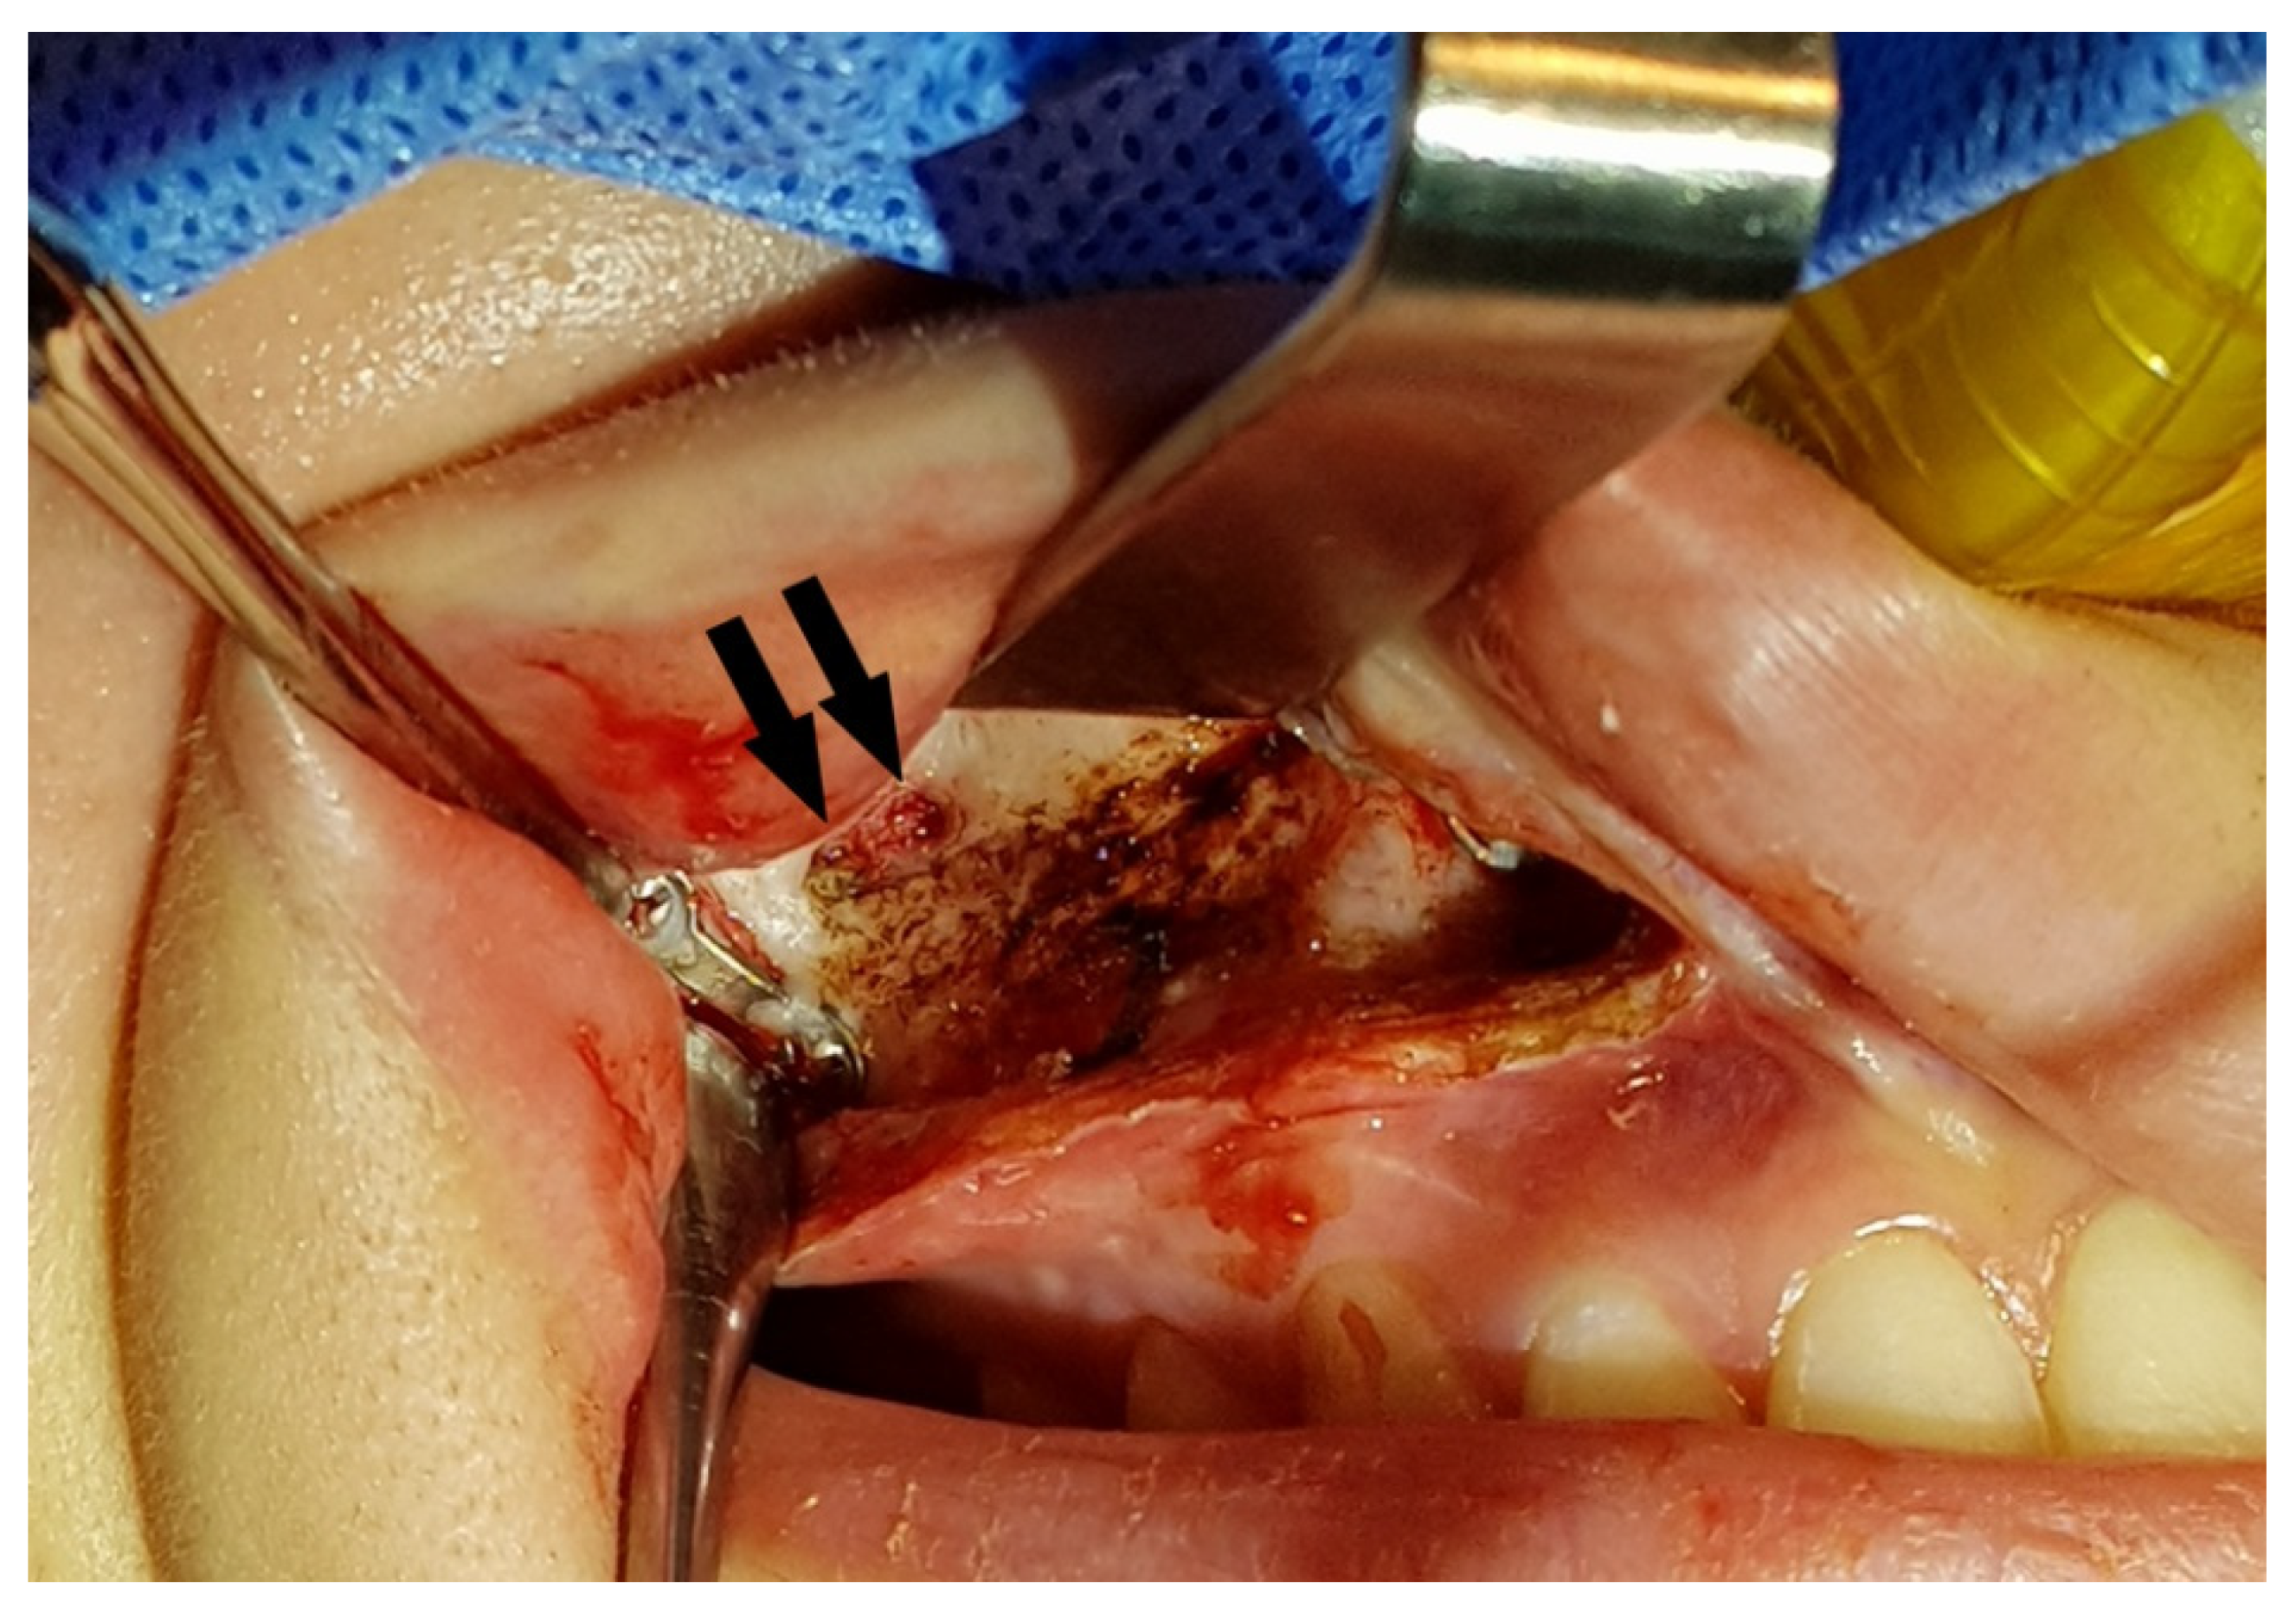

2. Materials and Methods